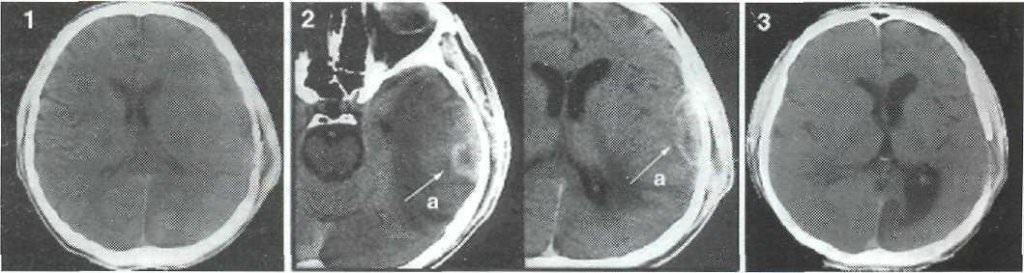

- 1 стадия (1-3 дня) наблюдается энцефалит – это начальное воспаление мозга. Самый легкий период, болезнь поддается излечению благодаря антибактериальной терапии или проходит самостоятельно путем рубцевания.

- 2 стадия (4-9 дней). В абсцессе уже образовался гнойник, который с каждым днем увеличивается в объёмах, если не обращаться к медикам.

- 3 стадия (10-13 дней). Вокруг гнойной полости образуется защитная пленка, которая не дает образованию распространяться дальше.

- 4 стадия (3 неделя). Пленка полноценно уплотнилась. В некоторых случаях начинается регресс болезни или вокруг капсулы образовываются новые очаги заражения.